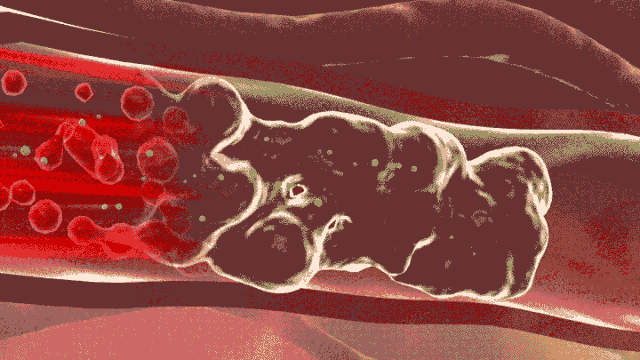

血管就好比一根根水管

血管里的代谢物和垃圾

就相当于水管里的“水垢”和“铁锈”

如果不注意清理和保养

时间长了,血管就会被彻底堵住

血管堵塞,血液不能流通